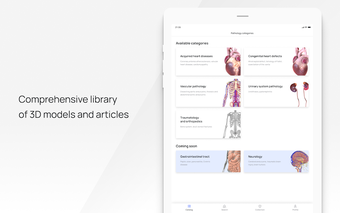

In this atlas of human pathologies you can learn about diseases, their causes, symptoms, and treatment. It contains all the essential information about the anatomy of the human body and its organs. You will be able to study diseases and their causes from an anatomy point of view. It contains information about diseases, their symptoms, and their treatment. In addition, you will be able to view 3D models of all the important organs of the human body.

All 3D pathology models are developed in close cooperation with medical experts of hospitals and research centers. They are thought out to the very smallest detail. Each category contains models of healthy organs.

VOKA Pathology 3D is an educational tool for medical students, lecturers, and physicians. It can help you learn about human anatomy and pathology.